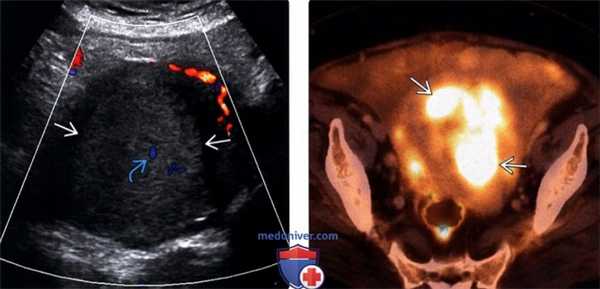

(Слева) Трансабдоминальная цветовая допплерография в поперечной плоскости: у пациентки в постменопаузе, которая обратилась с жалобами на вздутие живота, определяется крупное эхогенное объемное образование, растягивающее полость матки, и имеющее незначительный внутренний кровоток. Данные биопсии и мазка-отпечатка по Папаниколау подтвердили наличие светлоклеточного рака.

(Справа) Совмещенная ПЭТ/КТ с ФДГ, аксиальный срез: у этой же пациентки выявляется значительная метаболическая активность внутри объемного образования матки Также были выявлены метастазы в брюшине (не изображены).